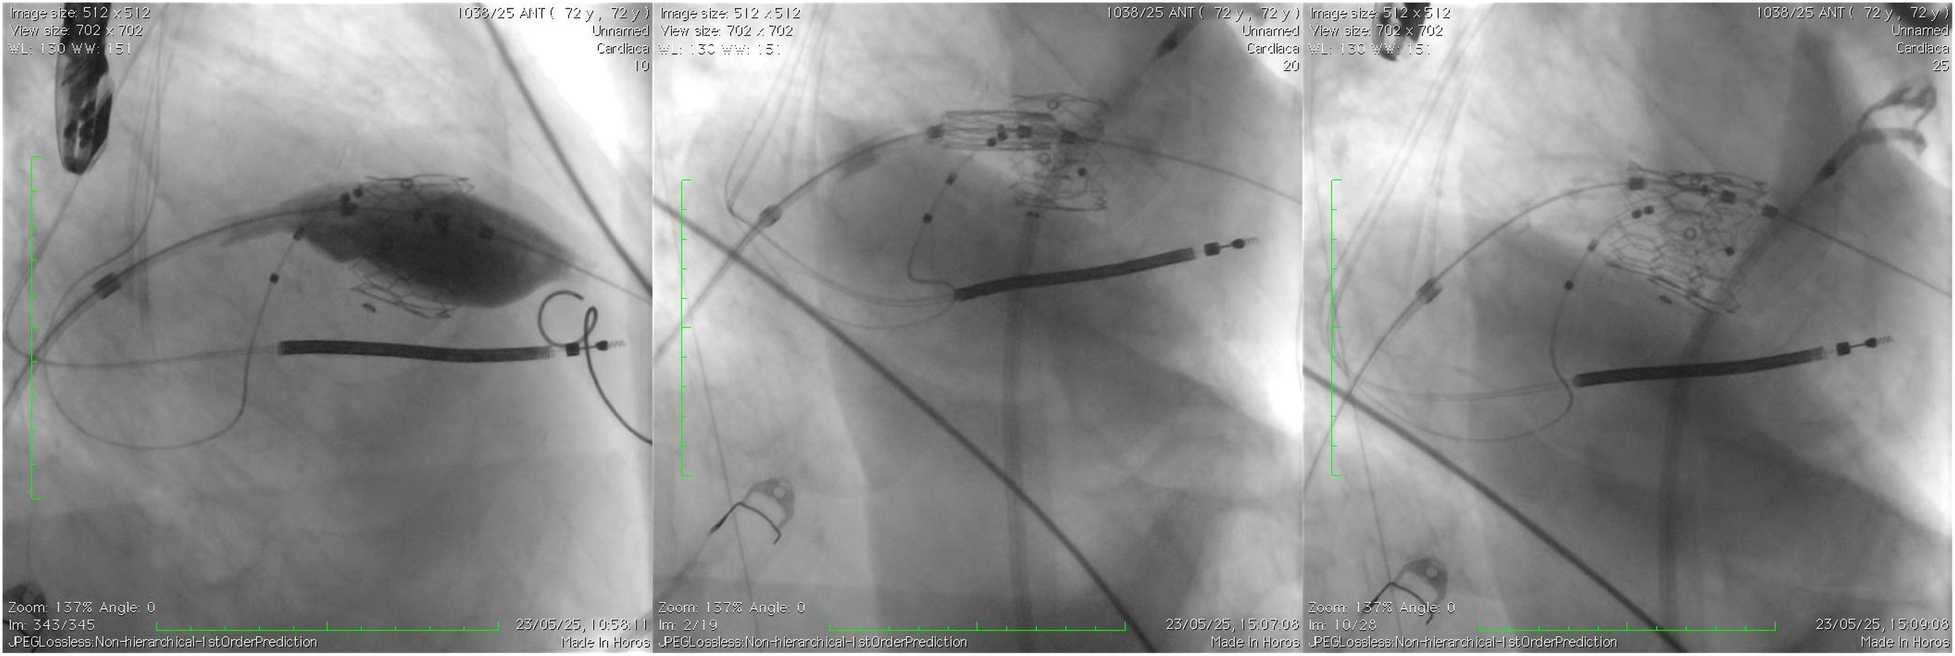

Figure 5

The deployment of the balloon-expandable valve.

Figure 6

The final fluoroscopy result of the new implanted valve (ViV TMVI).

Deployment of the balloon-expandable valve was performed under combined fluoroscopic and TEE guidance, confirming optimal alignment, full expansion, absence of PVL, and freedom from LVOT obstruction (Figures 5, 6).